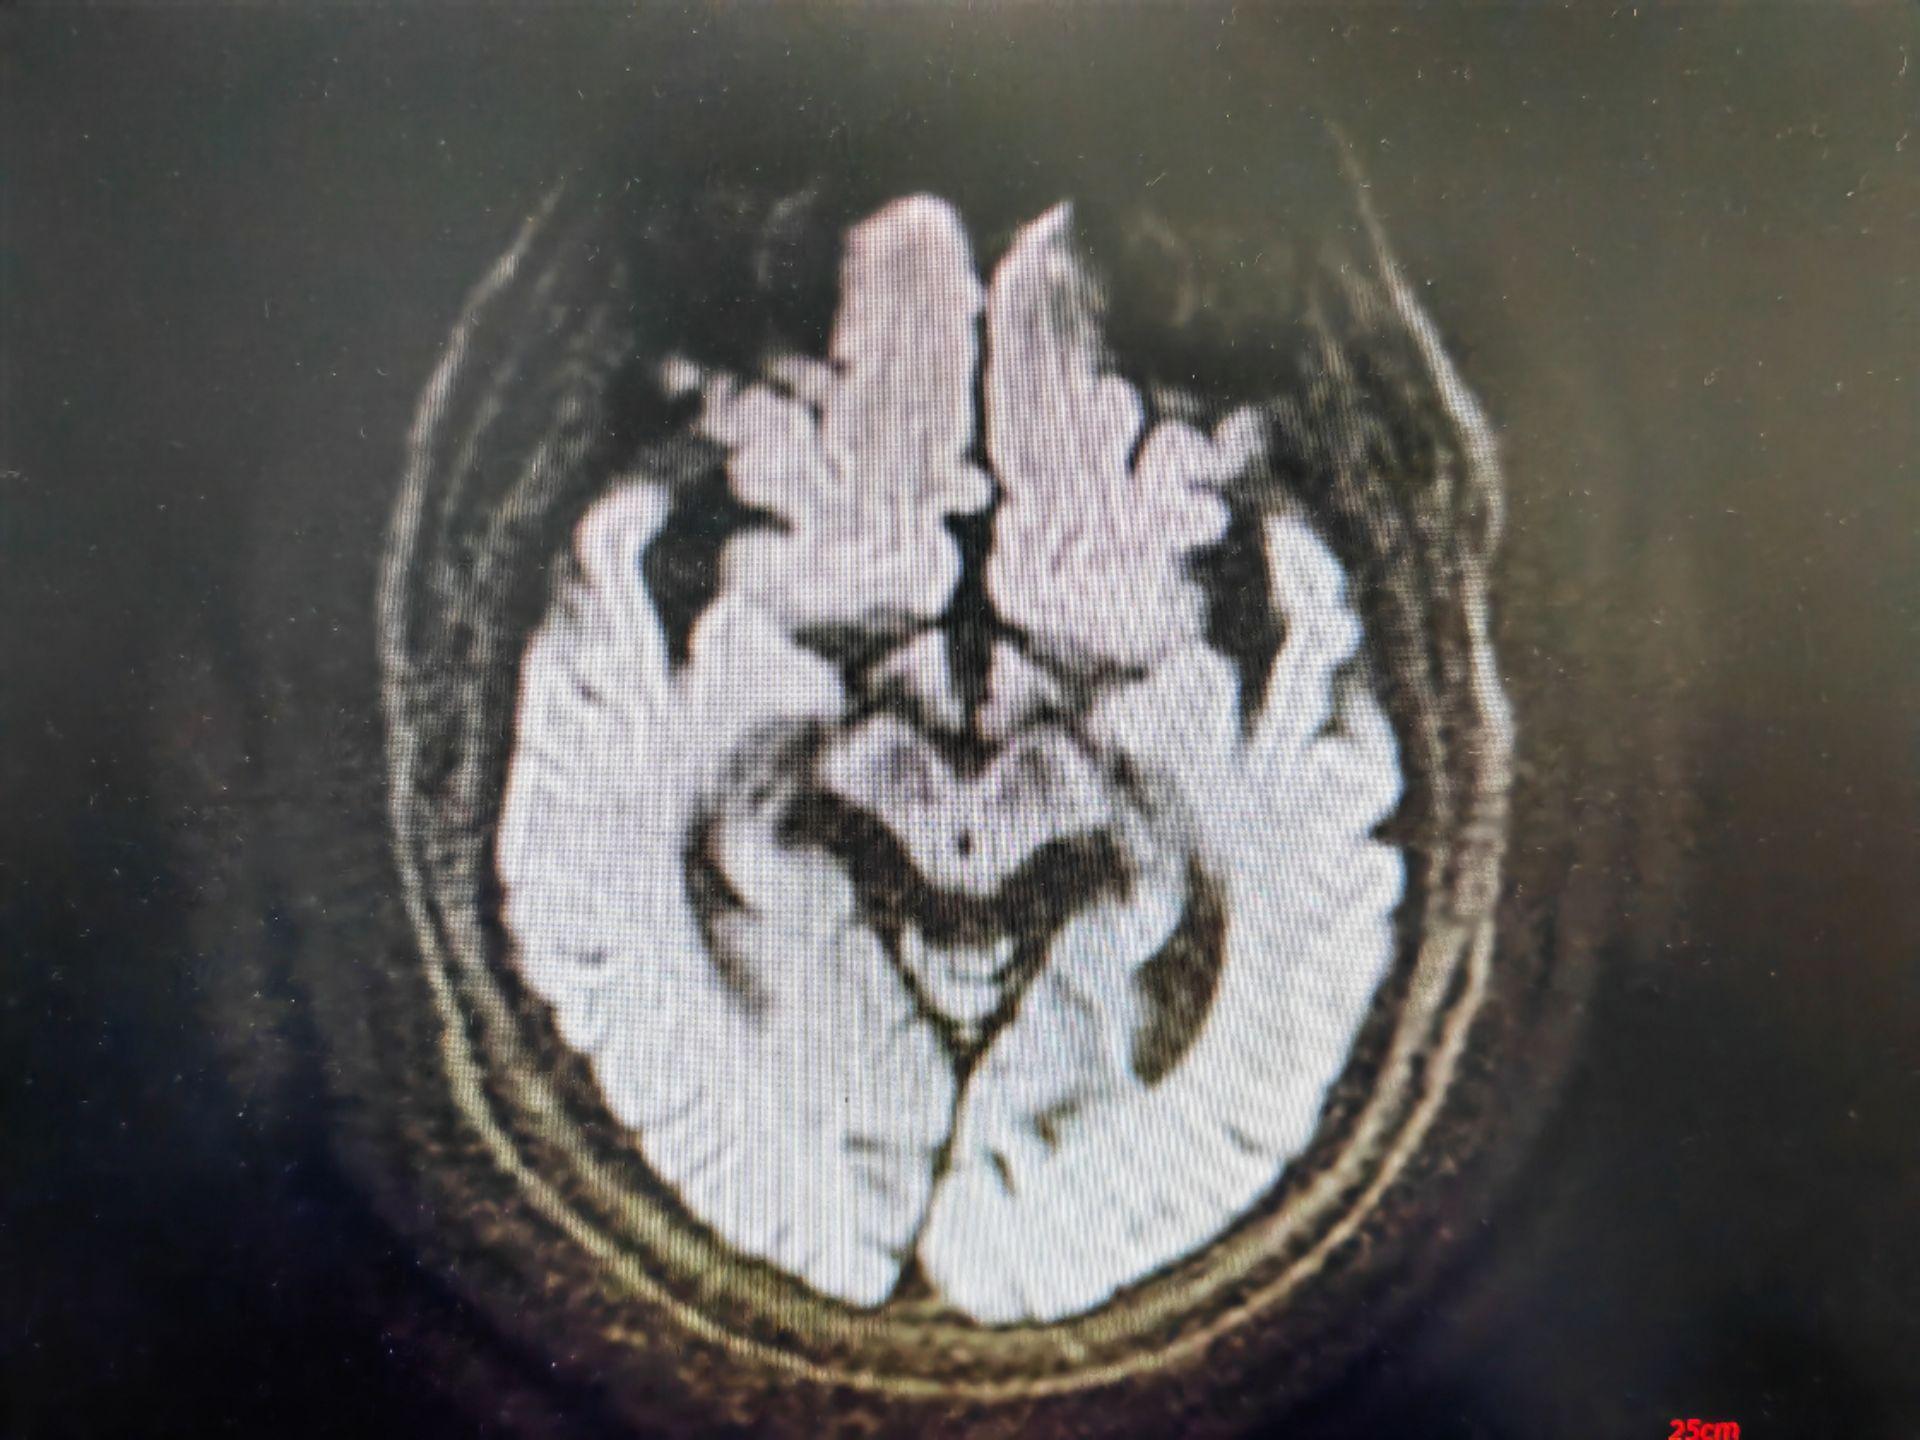

蜂鸟征,米老鼠征,牵牛花征。蜂鸟征 米老鼠征 牵牛花征 进行性核上性麻痹 PSP。PSP 是一种发生于中老年人的中枢神经系统变性疾病,临床表现为轴性强直,垂直性眼球运动障碍, 早期出现反复向后跌倒。但临床诊断为很可能 PSP 患者,经病理诊断证实的阳性预测率约 80%~90%。其临床病理特征为:中脑顶盖和被盖萎缩、黑质色素脱失,第三、四脑室及导水管轻度扩张。